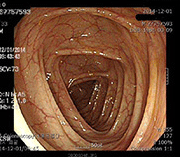

사례 1

치료 전 치료 전 장내 점막 사진